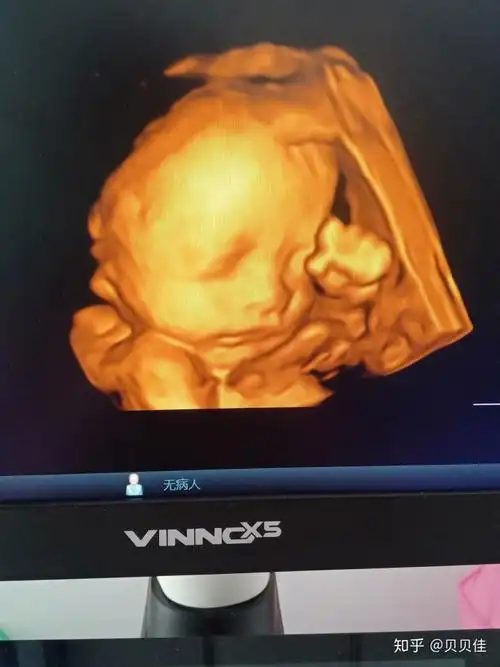

四维彩超图片,朋友们看看是女孩子是男孩子

四维彩超看到可爱的她正在揉眼睛

看四维彩超颜色就能看出性别

今天四维彩超归来 有图有真相.宝妈猜猜男女!只看楼主